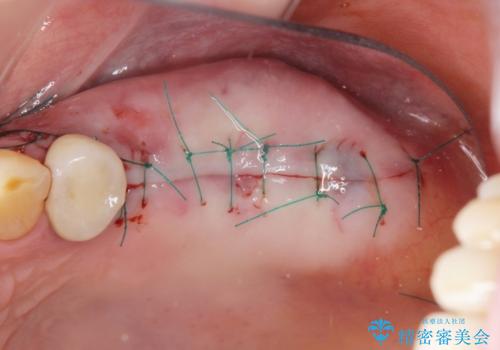

また十分な骨の厚みを確保するためソケットリフト法を併用し、長期的な安定を見込めるインプラント治療を実践します。

- 外科手術のため、術後に痛みや腫れ、違和感を伴います